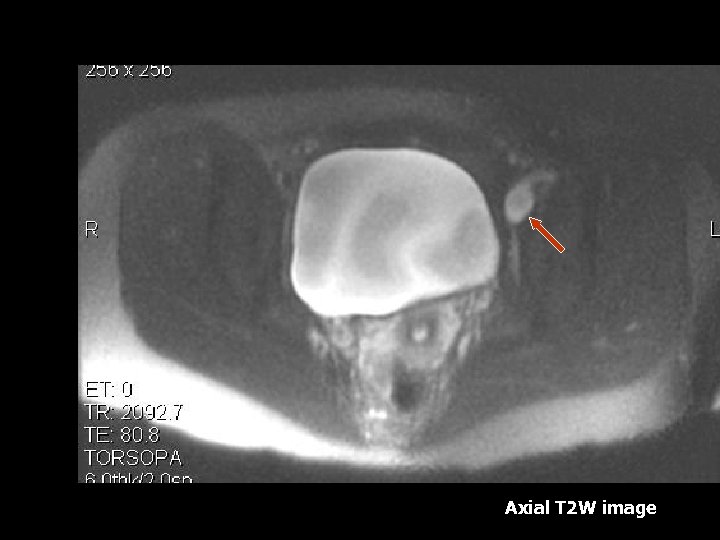

DVT • Ovarian and Pelvic vein thromboses are uncommon complication of preganancy(7). • MRI – Acutely thrombosed vessels are enlarged and contain low signal intensity thrombus(7). • Septic thrombus can cause streaky low intensity fat stranding on T 1 W images(7).

Axial SSFSE T 2 W image